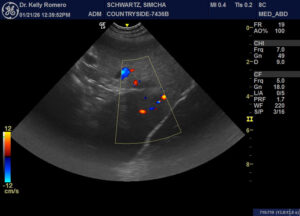

10 yr FS Shep cross with lethargy, weakness and dec. appetite. Concern for the hypoechoic splenic head. Could see vessels on doppler, but think they were attenuated to those in the body. Patient was not painful during the exam. FNAs of the spleen, irregular liver (nodular) and the hypoechoic cranial abdominal lesion shown in the last video are pending. Regarding the latter, no fluid obtained when aspirating other than for slide. Lesion ventral to the stomach and caudal to the liver, not in the region of the pancreas. How worried re spleen blood flow while aspirates pending?

splenic infarct, necrosis/abscess or sarcoma are my main diffs./ If nowhere else it needs to come out

Thank you, Eric. I need to confirm w/ referring vet, but owner thought the aspirates came back as sarcoma